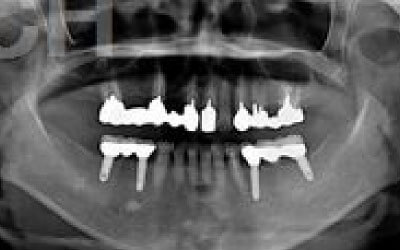

CTでは、骨や歯の状態を三次元で確認でき、正確な距離を測定することができます。

骨の厚さや傾き、神経の位置などを事前に詳しく計測することで、安全にインプラントを行うことができます。

しかし、事前にCTでしっかりと撮影し、三次元的に神経との距離を計測して治療計画を立てることで、心配は不要です。